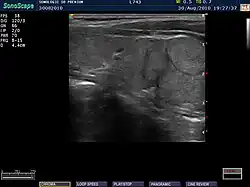

Ultrasound imaging of the thyroid gland (right lobe longitudinal) in a person with Hashimoto thyroiditis

Ultrasound

Ultrasound imaging of the thyroid showing Hashimoto's thyroiditis

An ultrasound may be useful in detecting Hashimoto thyroiditis, especially in those with seronegative thyroiditis,[13] or when patients have normal laboratory values but symptoms of autoimmune thyroiditis.[47] Key features detected in the ultrasound of a person with Hashimoto's thyroiditis include "echogenicity, heterogeneity, hypervascularity, and presence of small cysts."[13] Images obtained with ultrasound can evaluate the size of the thyroid, reveal the presence of nodules, or provide clues to the diagnosis of other thyroid conditions.[47]